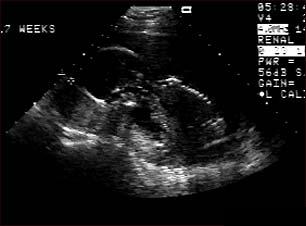

Ecografia fetala